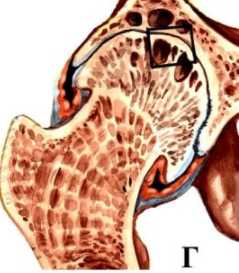

Как выглядит остеоартроз тазобедренного сустава

Это настолько давняя болезнь, что её признаки находят даже при раскопках древних захоронений. Сопровождается она разрушительными процессами в хрящевых пластинках суставов и проявляется следующими признаками:

- по краям суставов разрастается костная ткань;

- разрушение тканей носит дегенеративно-дистрофический характер;

- деформирующий процесс видоизменяет суставы.

Сравнительная характеристика тазобедренного сустава: сустав в нормальном состоянии и поражённый остеоартрозом

Хрящи, расположенные на окончаниях суставов, обеспечивают последним защитную амортизацию для нормальной подвижности нижних конечностей. В здоровом состоянии кости мягко скользят, не создавая при этом никакого трения. Стоит только хрящу заболеть, и эта комфортность сразу же исчезает.